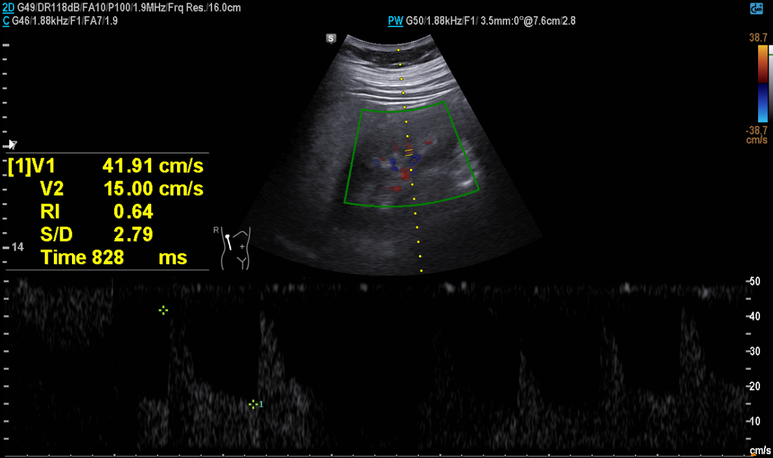

부신 우연종은 없었으며 RI는 정상 범위의 상한선 소견, 이외 중등도의 지방간 소견